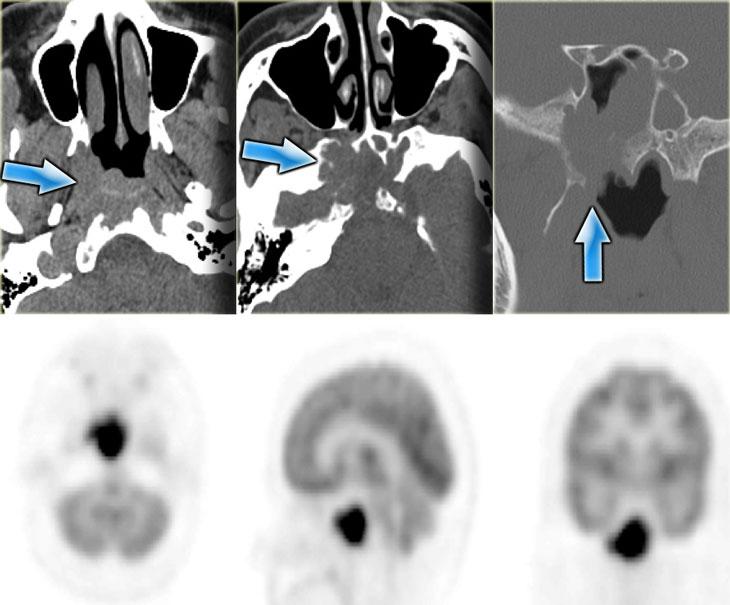

Bên trái là hình ảnh CT của một bệnh nhân sau ghép phổi có sốt và liệt nhiều dây thần kinh sọ tiến triển nhanh.

Chúng tôi sẽ trình bày hình ảnh CT và MRI của bệnh nhân này. Chẩn đoán u lympho được xác định qua sinh thiết.

Trước tiên hãy nghiên cứu các hình ảnh để đánh giá mức độ lan rộng của bệnh.

Trên hình ảnh CT, các phát hiện bao gồm:

- Khối mô mềm trong xoang hàm (mũi tên đỏ).

- Phá hủy thành xoang (mũi tên vàng).

- Tái cấu trúc và phá hủy xương chân bướm (mũi tên xanh dương).

- Khối mô mềm lớn trong khoang cơ nhai (dấu hoa thị).

Hình ảnh bên phải ở mức cao hơn.

Có hình ảnh mờ đục xoang bướm kèm phá hủy và loãng xương bướm.

CT thể hiện rõ sự phá hủy xương và một phần xâm lấn mô mềm.

Bên trái là hình ảnh MRI tương ứng.

Các phát hiện bao gồm:

- Dịch trong xoang bướm phải (mũi tên đỏ).

- Mô giảm tín hiệu trong xoang bướm trái (mũi tên vàng).

- Lan rộng dọc theo bờ màng cứng của hố sọ giữa (mũi tên xanh dương).

- Lan rộng vào khoang gò má-cơ nhai trái (mũi tên vàng lớn).

- Sau tiêm thuốc tương phản từ, không có ngấm thuốc dạng đặc của mô trong khoang bướm.

Tiếp tục xem hình ảnh mặt phẳng coronal.

Hình ảnh mặt phẳng coronal của cùng bệnh nhân: T1 trước và sau tiêm thuốc tương phản từ.

Hình ảnh bình thường của hang Meckel bên phải; mô trong hang Meckel bên trái lan rộng vào xoang hang (mũi tên xanh dương).

Mũi tên đỏ chỉ vào bờ màng cứng của xoang hang: có ngấm thuốc ở cả hai mặt của màng cứng.

Bệnh lý bao quanh thùy thái dương (mũi tên xanh lá) và lan xuống dưới qua lỗ bầu dục (mũi tên vàng) vào khoang cơ nhai.

Dấu hoa thị chỉ mô bình thường không ngấm thuốc trong khoang cơ nhai.

Bệnh nhân này bị u lympho.

Chín trong mười trường hợp, bệnh nhân suy giảm miễn dịch sẽ bị nhiễm nấm, một trong mười trường hợp sẽ là u lympho.

CT và MRI có vai trò bổ sung cho nhau trong trường hợp này, nhưng cuối cùng cần sinh thiết để phân biệt hai chẩn đoán này, vì phương pháp điều trị khác nhau.